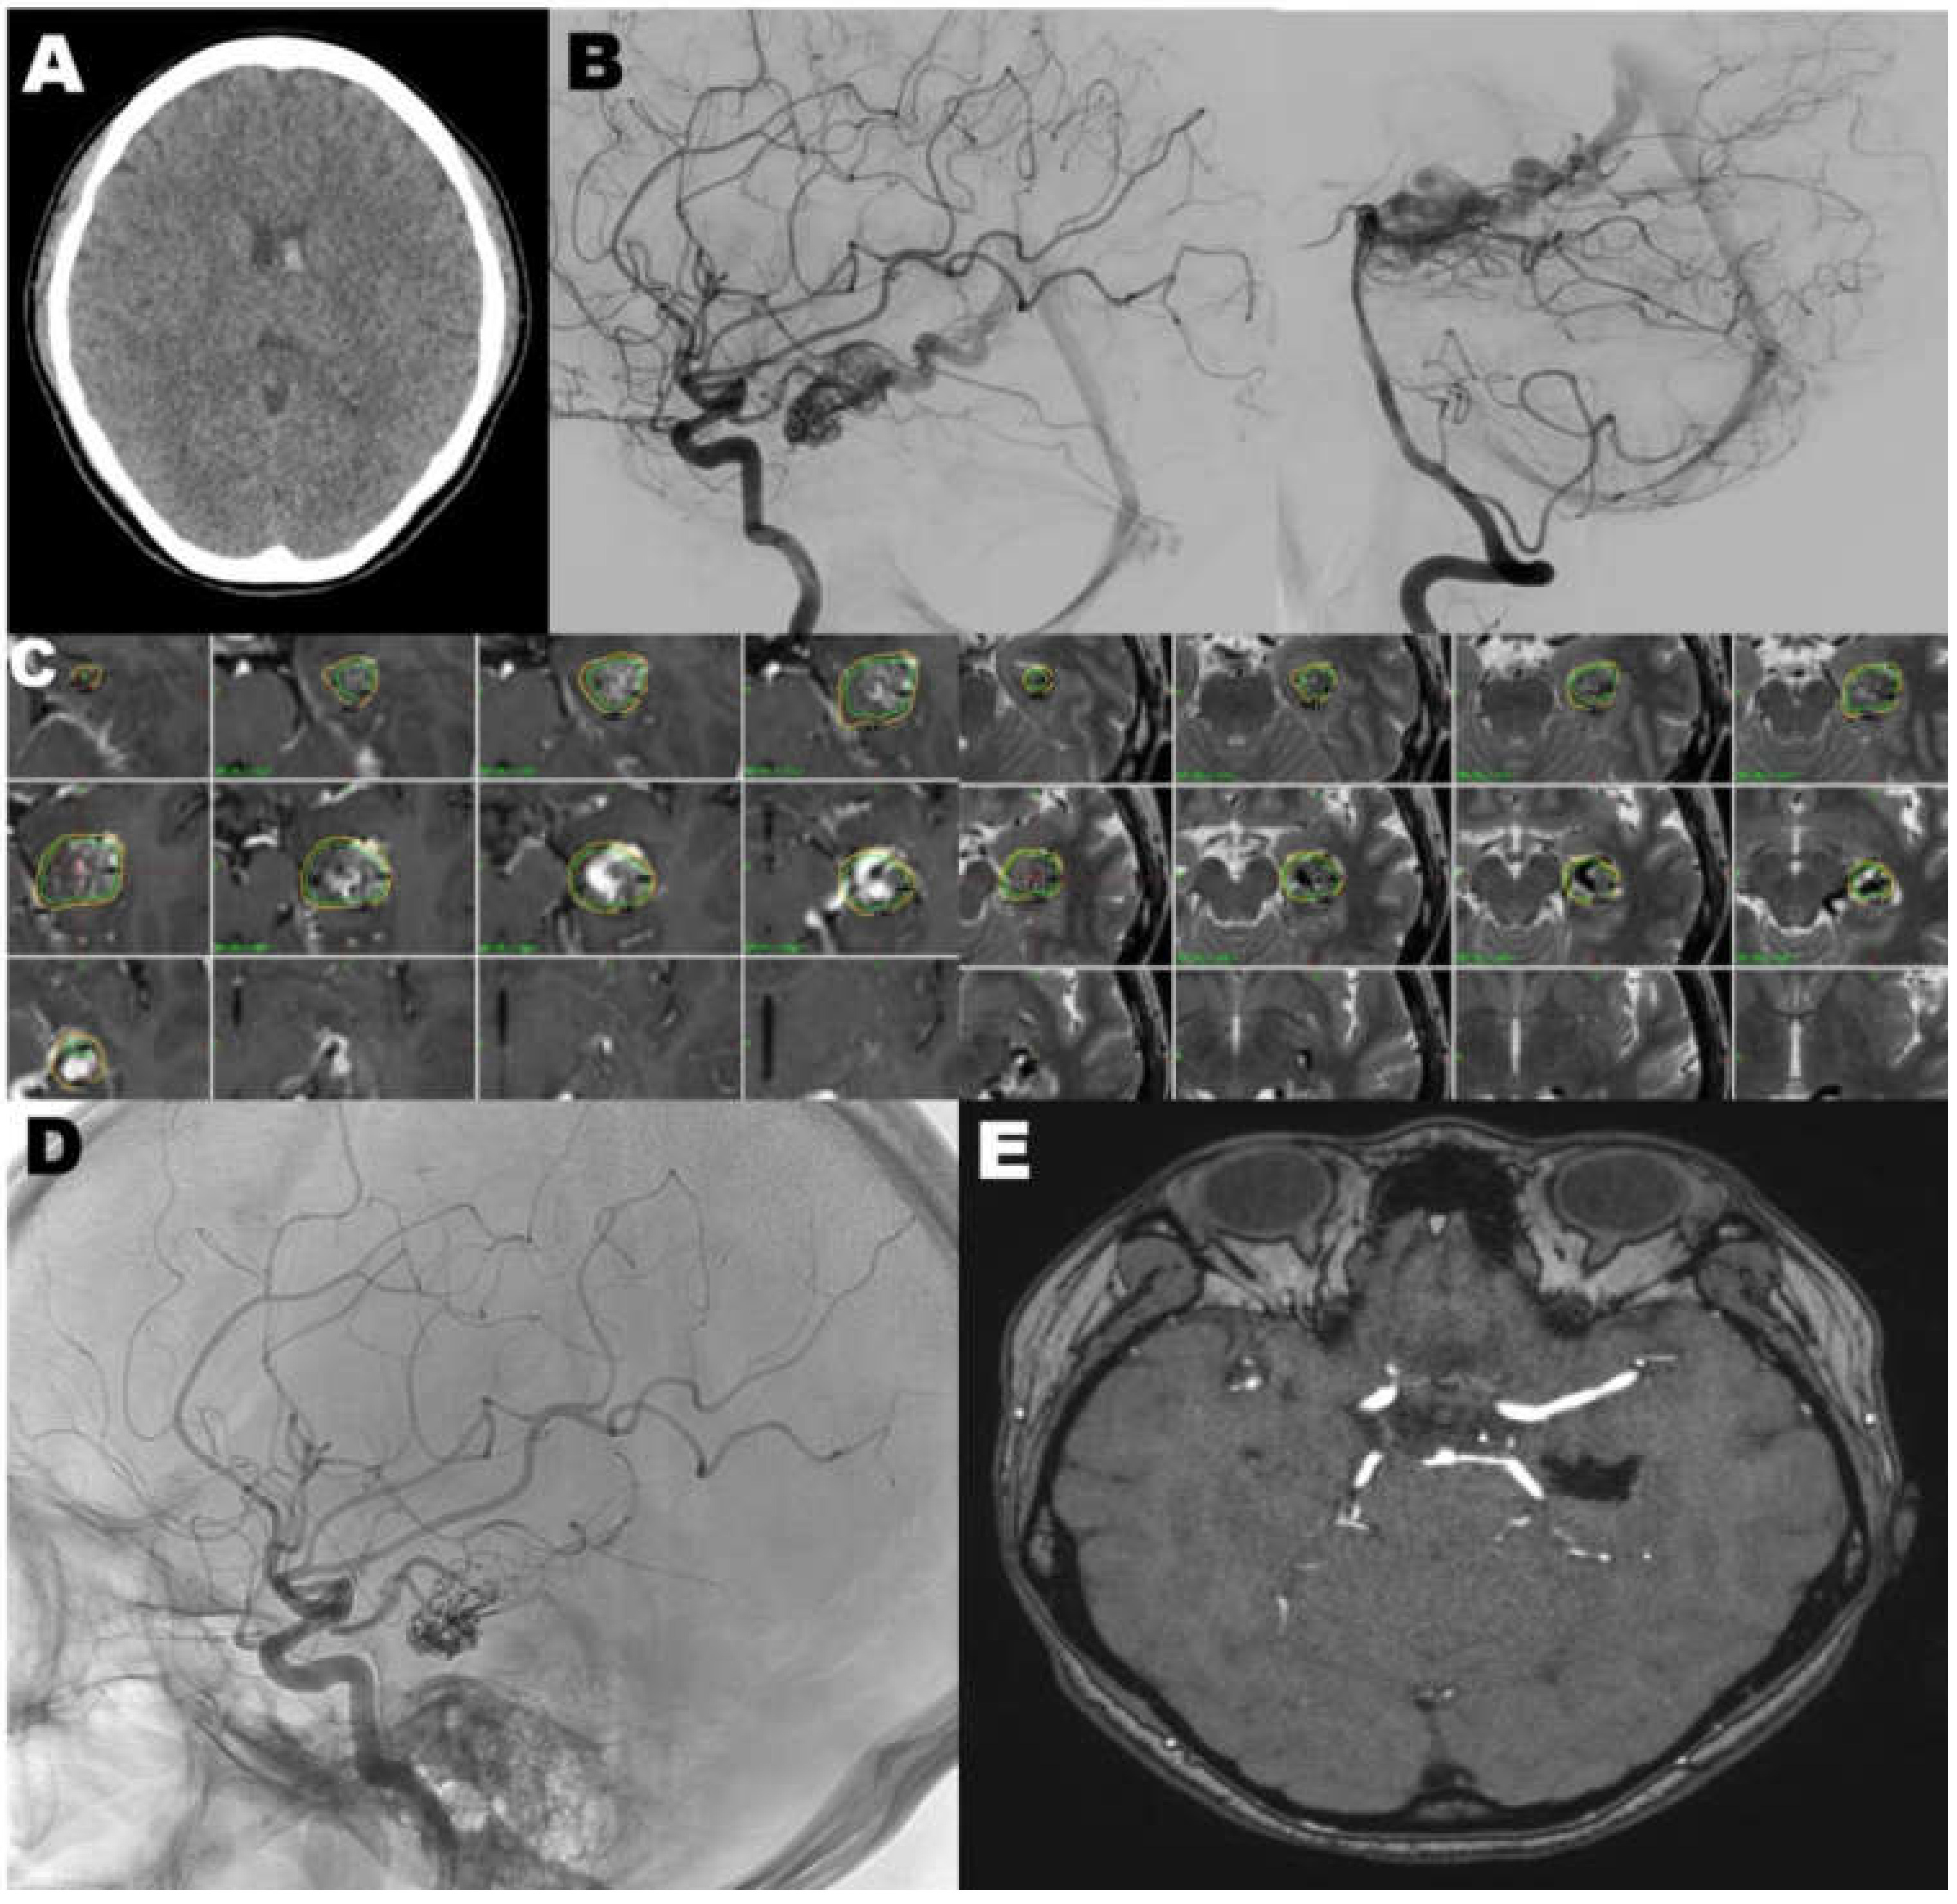

4.1. Case 1